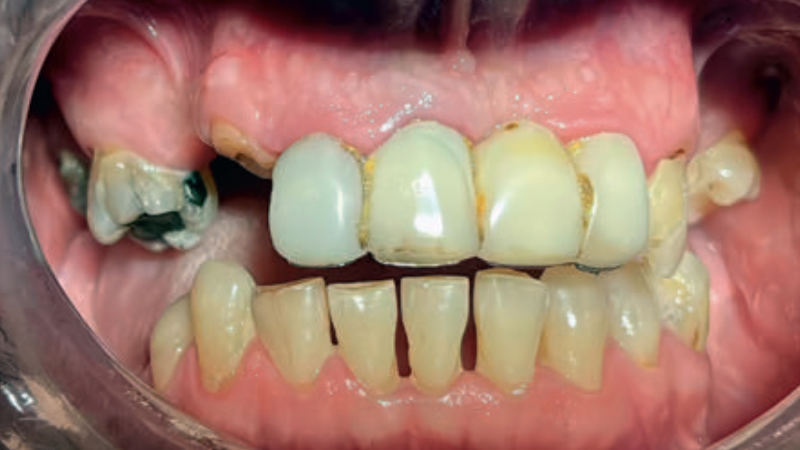

- Pacjent zgłosił się do Poradni Protetyki Stomatologicznej celem wymiany nieszczelnego mostu metalowo-akrylowego w odcinku przednim szczęki. Zależało mu również na poprawie estetyki i uzupełnieniu braków międzyzębowych.

Streszczenie: W artykule opisano przypadek dwuetapowego leczenia protetycznego z wykorzystaniem natychmiastowej protezy tymczasowej. Docelowo tkanki zębów oraz zęby w szczęce i żuchwie zostały odbudowane z wykorzystaniem uzupełnień stałych i protez szkieletowych. Przeprowadzone leczenie pozwoliło na stopniową adaptację do nowych warunków i utrzymanie właściwych relacji pomiędzy mięśniami żucia, językiem i stawami skroniowo-żuchwowymi przed oddaniem pracy ostatecznej, co miało pozytywny wpływ na przewidywalność terapii.

Summary: The article describes a case of a two-stage prosthetic treatment using an immediate temporary denture. Ultimately, maxillary and mandibular tooth tissue as well as missing teeth were reconstructed using permanent restorations and skeletal dentures. Performed treatment allowed for gradual adaptation to the new conditions and maintenance of proper relationships between the masticatory muscles, tongue and temporomandibular joints, before the final restoration was placed, which positively impacted the predictability of the treatment.